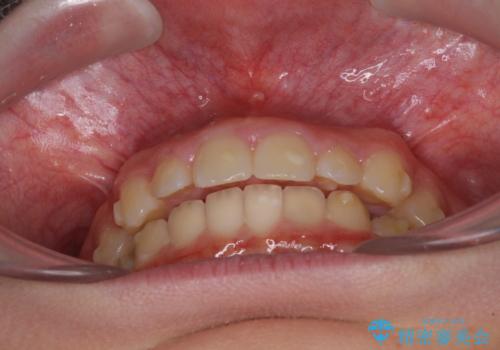

- ヨーロッパにてインビザライン矯正を始めたものの、日本に転居することになり、治療の継続を希望して来院された患者様です。

治療計画に無理がなく、現地担当医と速やかに連絡が取れるとのことで、インビザライン社での転医手続きを行い、継続して治療を行うこととしました。

舌の突出癖により、上下前歯が非接触となっていたため、トレーニングを徹底的に指導し、安定した咬み合わせにより終了させることができました。